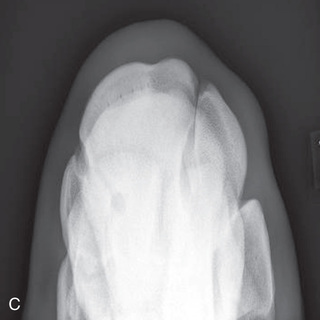

The three following views can be taken for the dorsoproximal-palmarodistal (DPr-PaDi) views of the foot. The terminology changes slightly depending on the actual positioning. Because the foot or the beam is at an angle to the ground, the high coronary and upright pedal routes are technically termed DPr-PaDiO views. Note that there is no lateral or medial distinction, so do not get confused.

The D65Pr-PaDiO view projects both borders and extremities of the navicular, and the distal border can be seen through the distal and palmar (plantar) portions of the middle phalanx (Fig. 24.15).

The D45Pr-PaDiO view projects the proximal border and extremities.